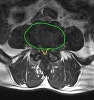

MRI : 요추 척추관협착증(Lumbar spinal stenosis)

- MRI : 협착증 진단에 가장 우수한 검사